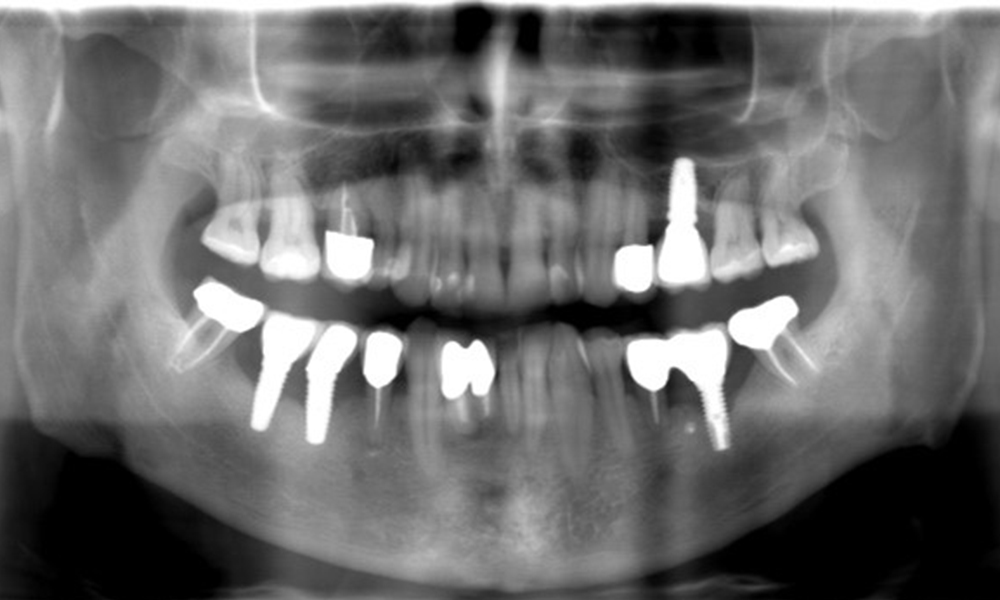

52-годишен пациент се явява на профилактичен преглед. Пациентът няма хронични заболявания и не приема никакви лекарства. Претърпял е различни дентални лечения и също така има две активни кариозни лезии. Освен това има четири импланта (2-ри, 3-ти и 4-ти квадрант). Установява се, че има ранно пародонтално заболяване (стадий IV, степен В). Състоянието на пародонта е стабилно, като дълбочина на сондиране (ST) от 5 mm се проявява само при импланта в област 36. Установен е и гингивит.

В историята на заболяването на пациента няма особени рискови фактори със специфични дентални последици. Следователно ключовият фактор е изискването по отношение на оралното здраве. В това отношение има данни за дълбочина на сондиране от 5 mm при импланта в 3-ти квадрант, а на рентгеновата снимка - за увеличена костна загуба. Пациентът също така има стабилно понастоящем пародонтално заболяване и две активни начални кариозни лезии.